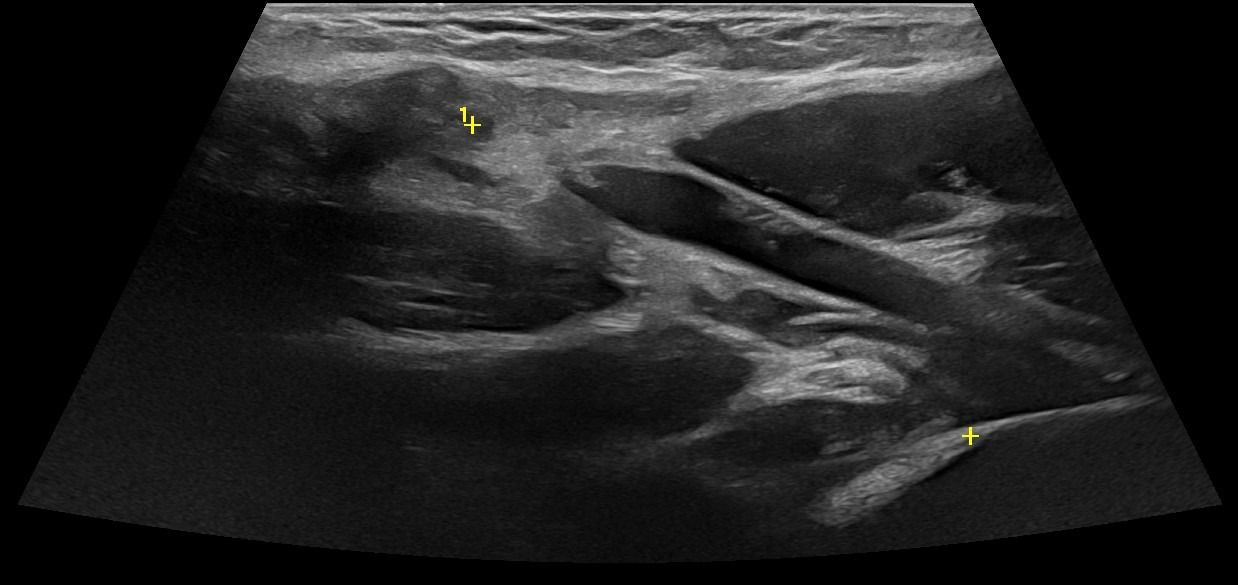

Elbow Ultrasound provides comprehensive imaging of various structures in the region, allowing the identification of pathologic conditions in the joint, bursae, tendons, ligaments, nerves, and soft tissues of the elbow.

- Fluid collection in the elbow joint (i.e. hemarthrosis)

- Fluid collection in the bursa (i.e olecranon bursitis)